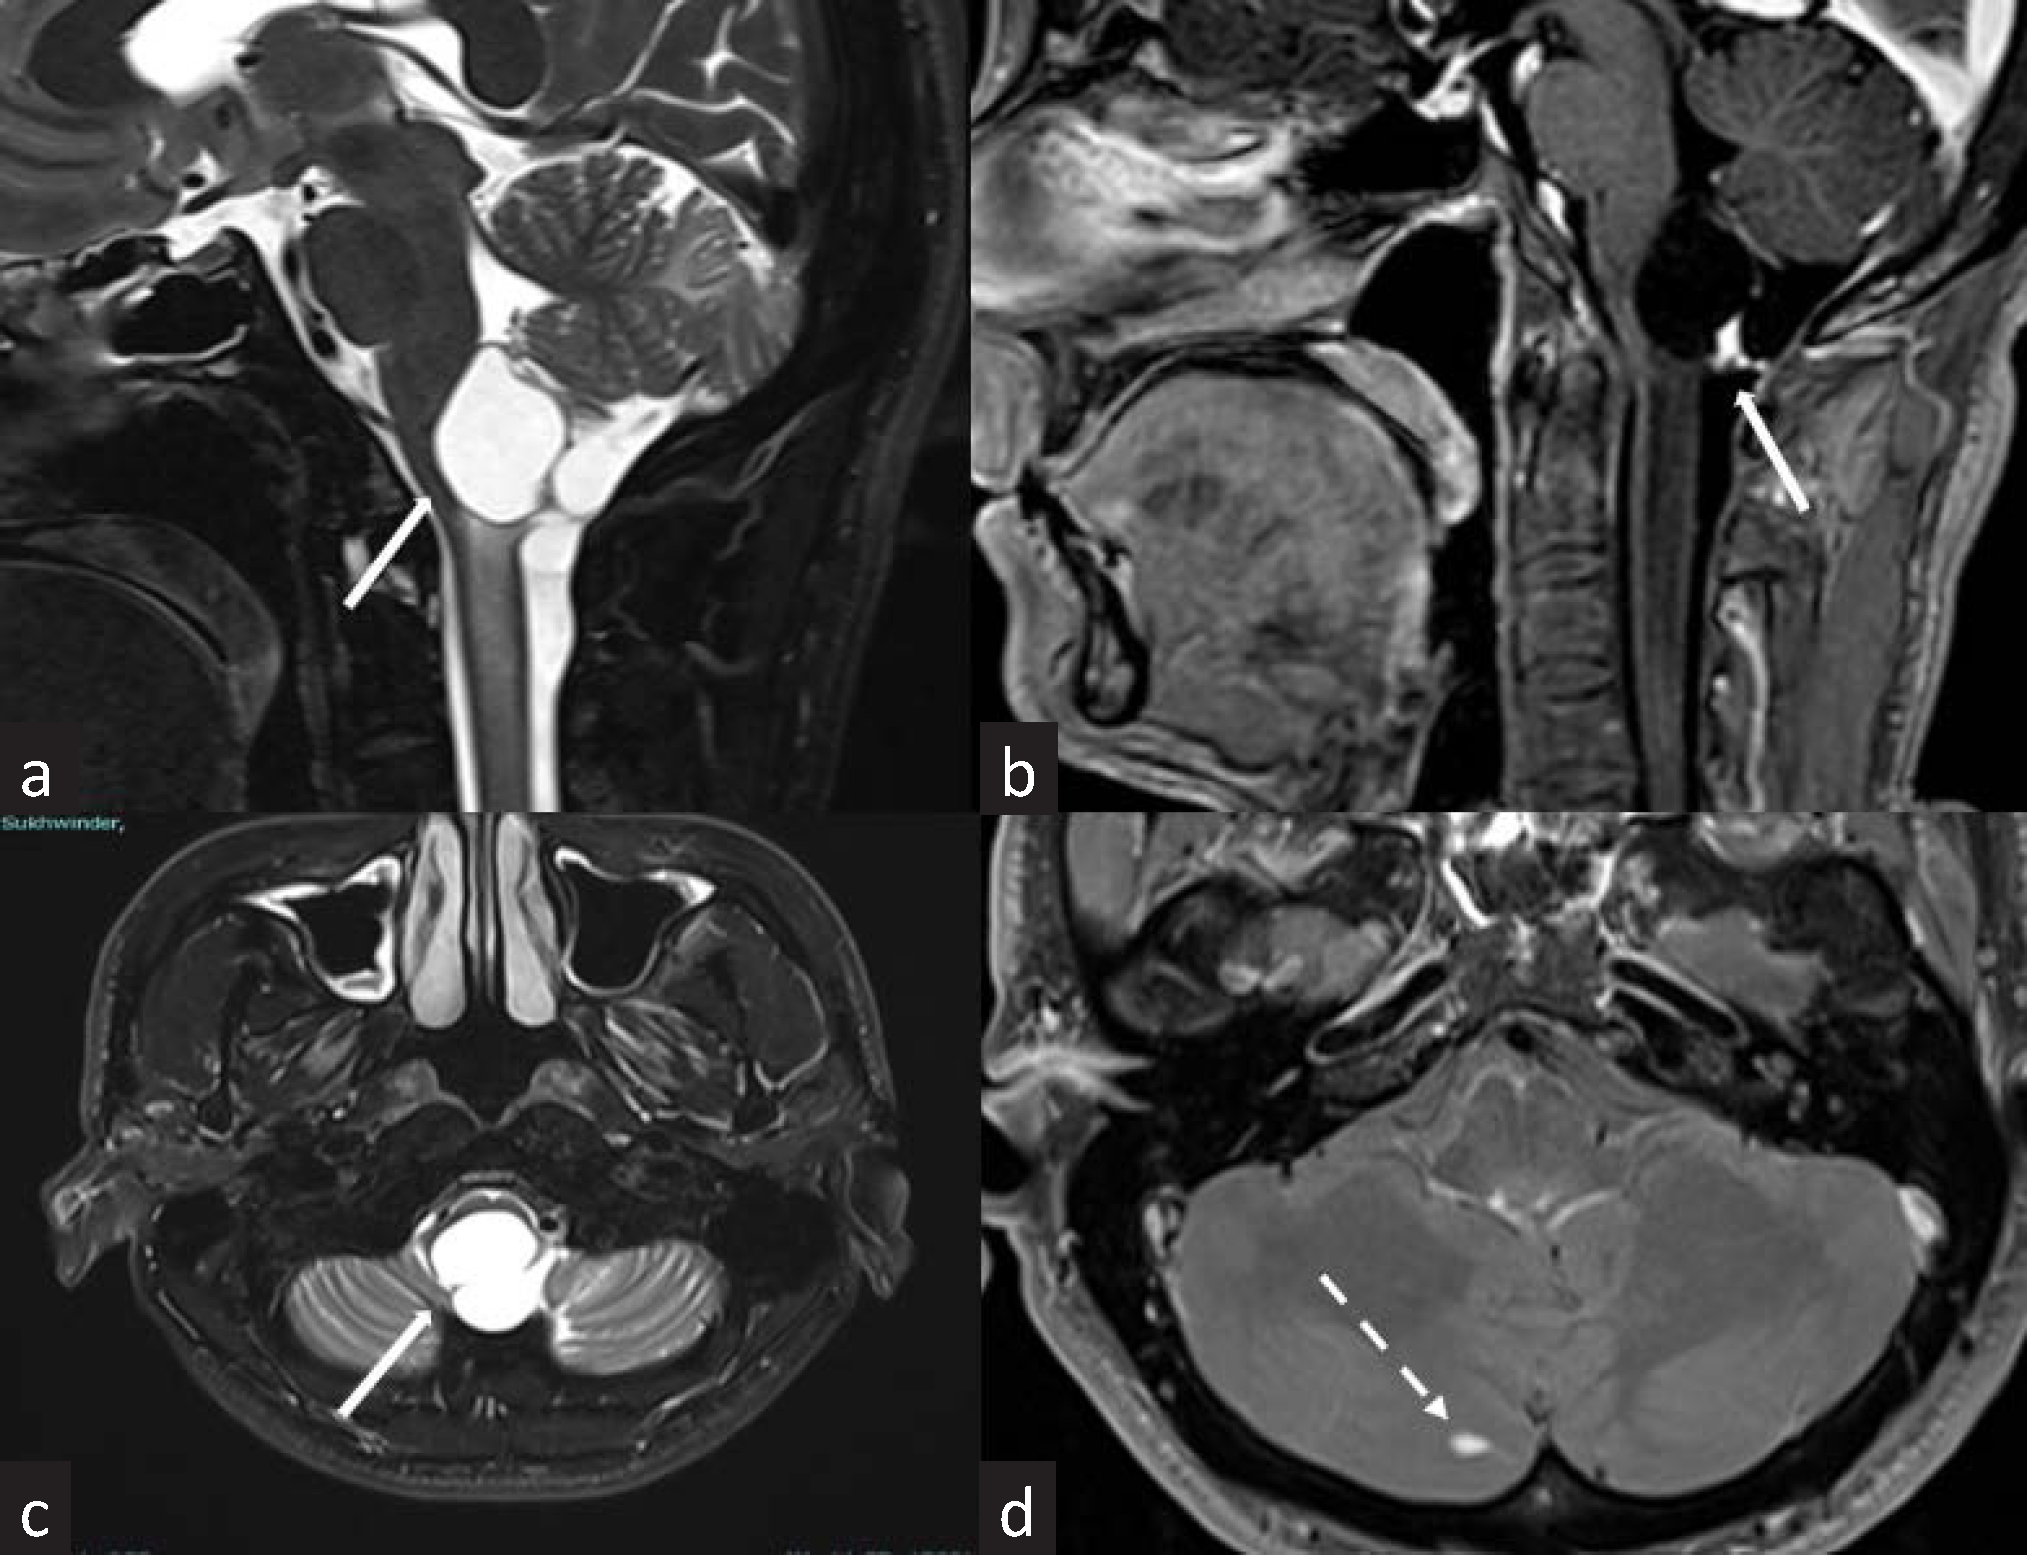

- MRI images of brain and cervical spine of a 34-year-old man with VHL. (a-c) Sagittal and axial T2 weighted and postcontrast images reveal a well-defined T2 hyperintense cystic lesion with hyperenhancing mural nodule within the dorsal aspect of the medulla: hemangioblastoma (solid white arrows). (d) Axial postcontrast images show a small intensely enhancing area in the right cerebellar hemisphere: cerebellar hemangioblastoma (dashed white arrow). VHL: Von-Hippel-Lindau.